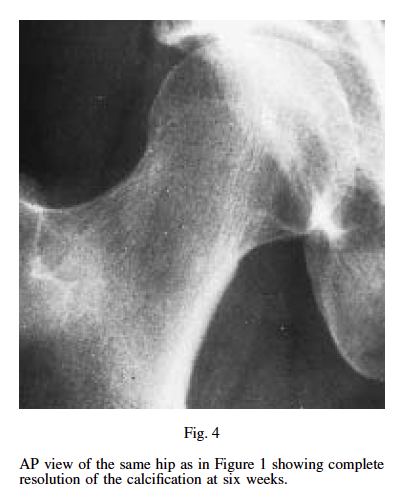

타박상 후 발생한 골화근육염의 충격파 치료결과 - 2주, 6주 치료후 석회화 사라지는 논문

Clinical Features: A 20 year-old male semiprofessional rugby player presented with progressive pain and loss of range of motion after sustaining a severe, right quadriceps contusion nine weeks earlier. The differential diagnosis of myositis ossificans was suspected and confirmed on radiographic examination.

Intervention and Outcome: A two week treatment protocol was undertaken consisting of three sessions of extracorporeal shockwave therapy and an unsupervised exercise program consisting of active and passive range of motion, gradual strengthening and balance exercisesThe patient experienced appreciable improvements in pain and range of motion in two weeks and was able to participate in sport specific activity four weeks after presentation.

Summary: This case illustrates the successful conservative management of post-traumatic myositis ossificans of the anterior thigh with extracorporeal shockwave therapy and a primarily unsupervised graded exercise program within a condensed treatment time frame of 2 weeks.